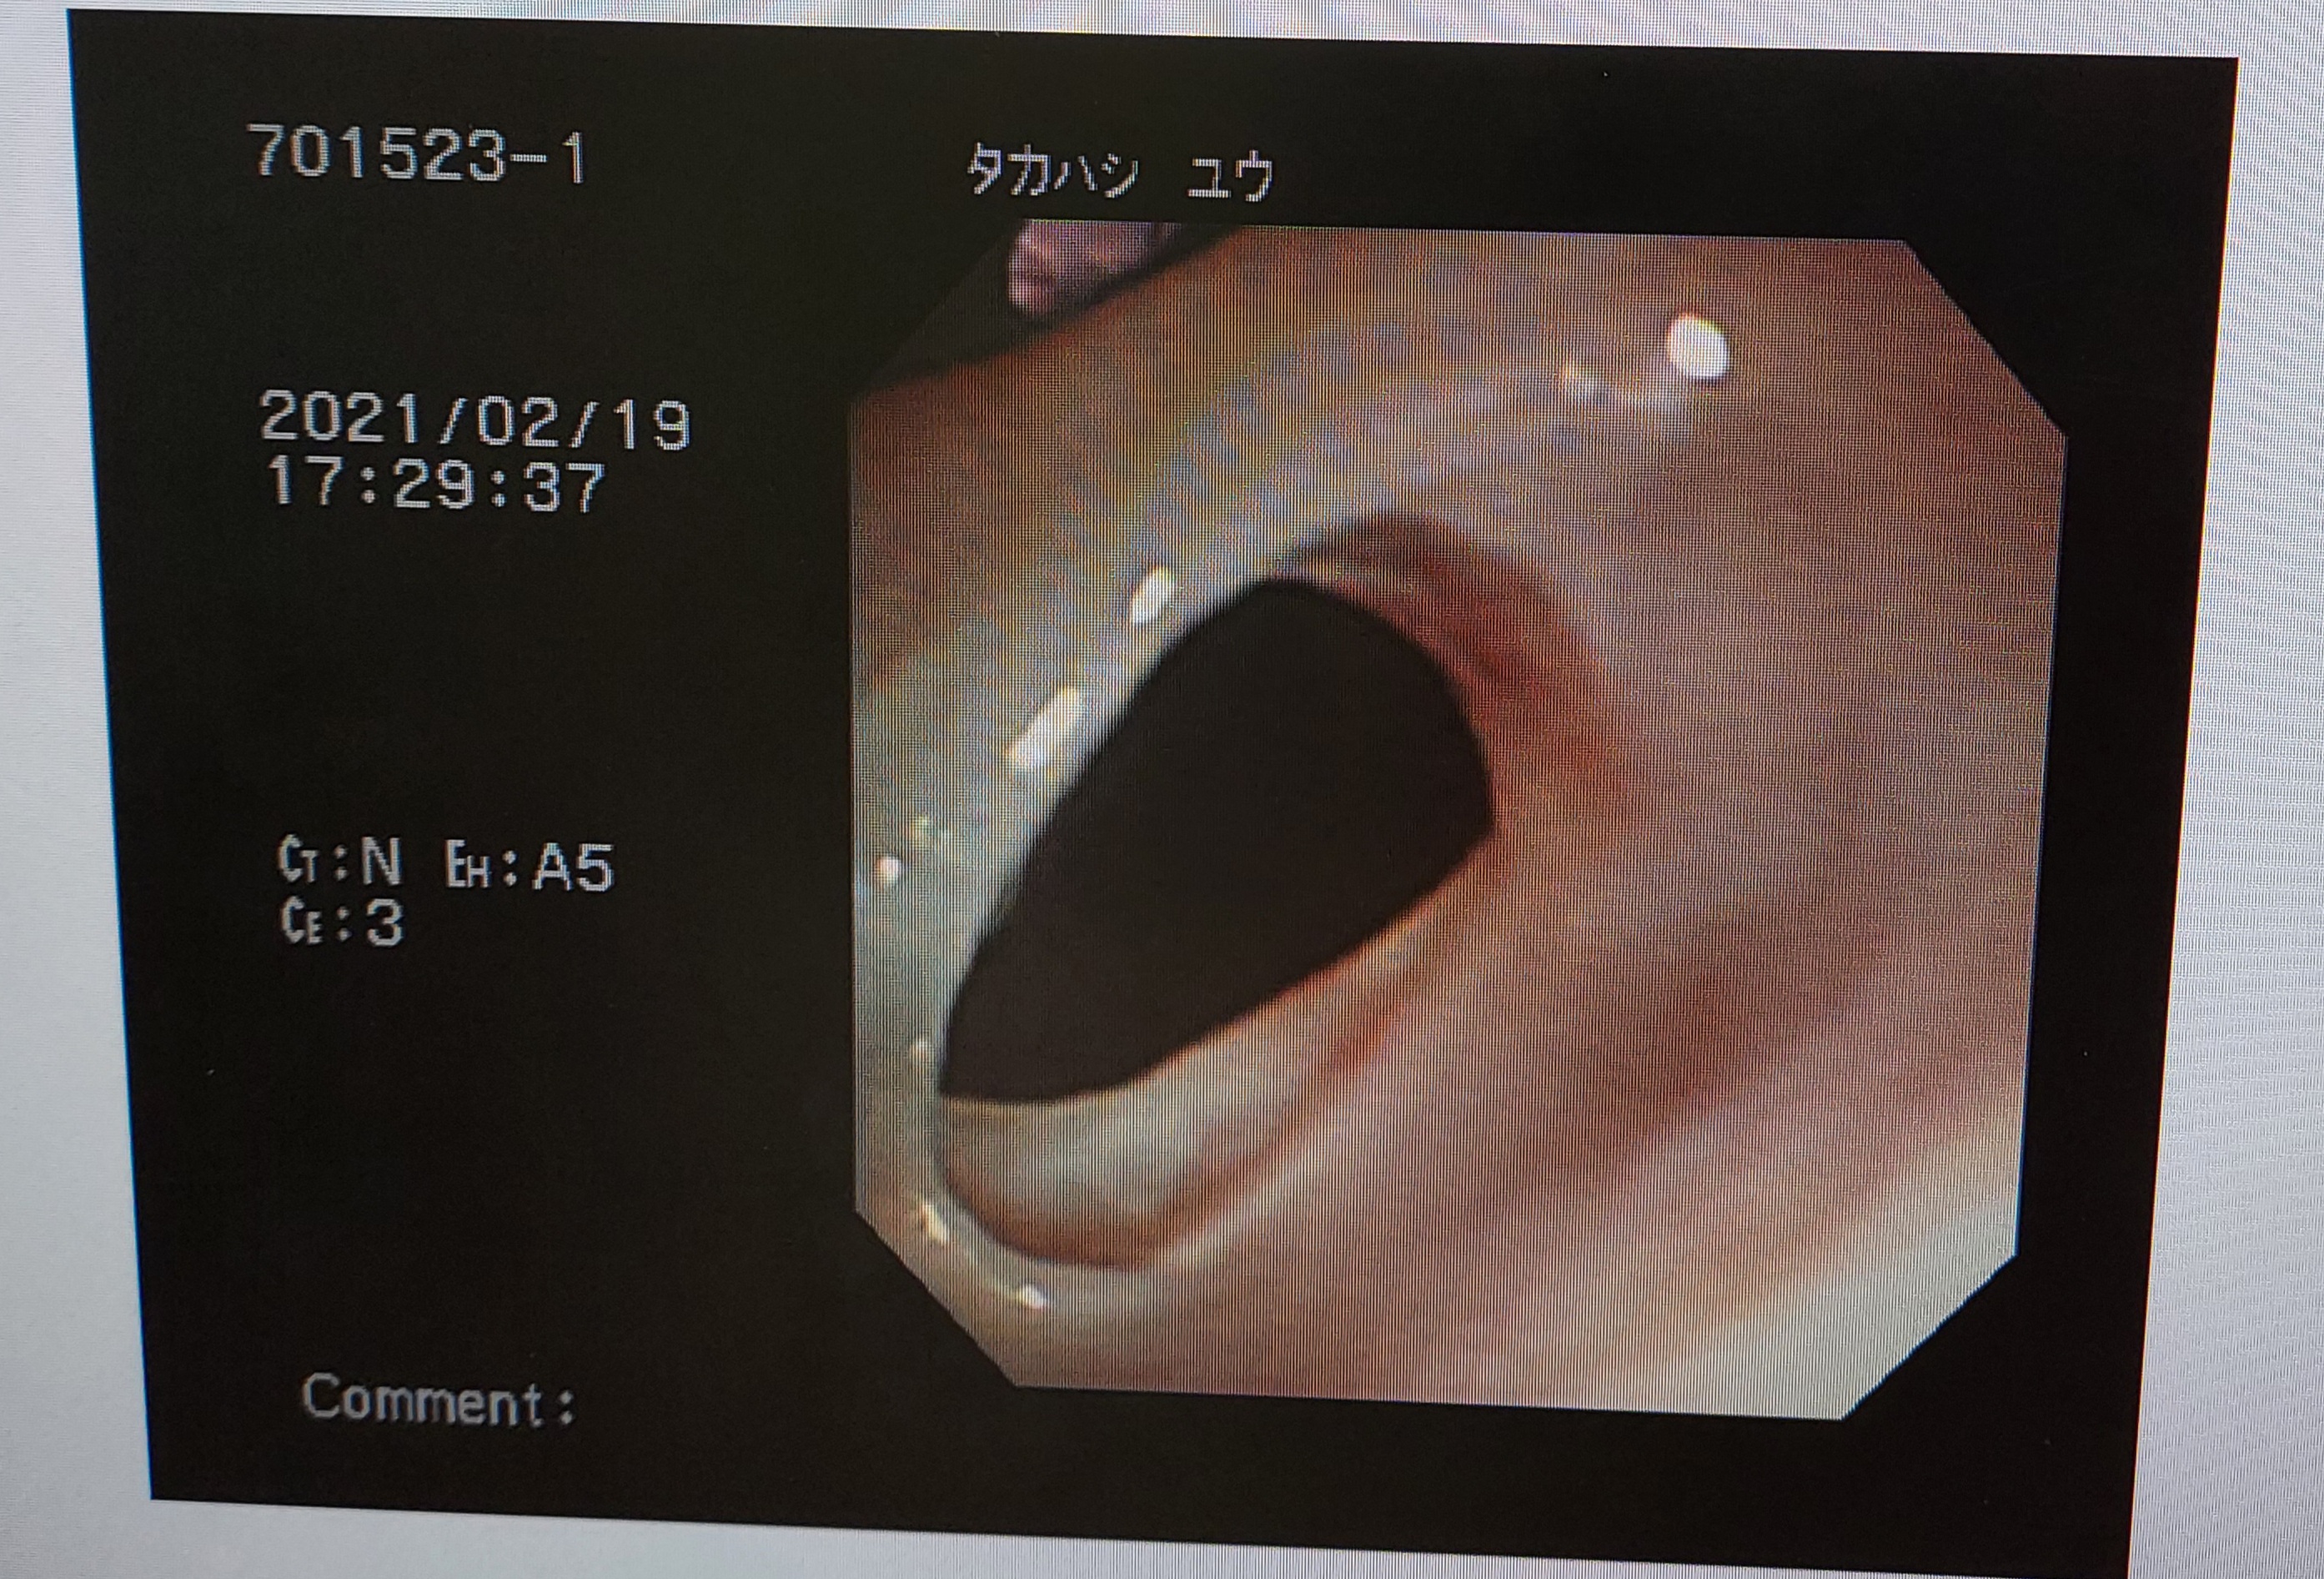

内視鏡で鼻腔から咽頭部にかけてのあたりにあった膜を破って通りを良くしたゆうくん。

こんなに狭窄していたのを

鼻孔から咽頭部へのあたり、こんな膜が出来てしまいかろうじて小さな穴で呼吸や呑み込みが出来ている状態でした。